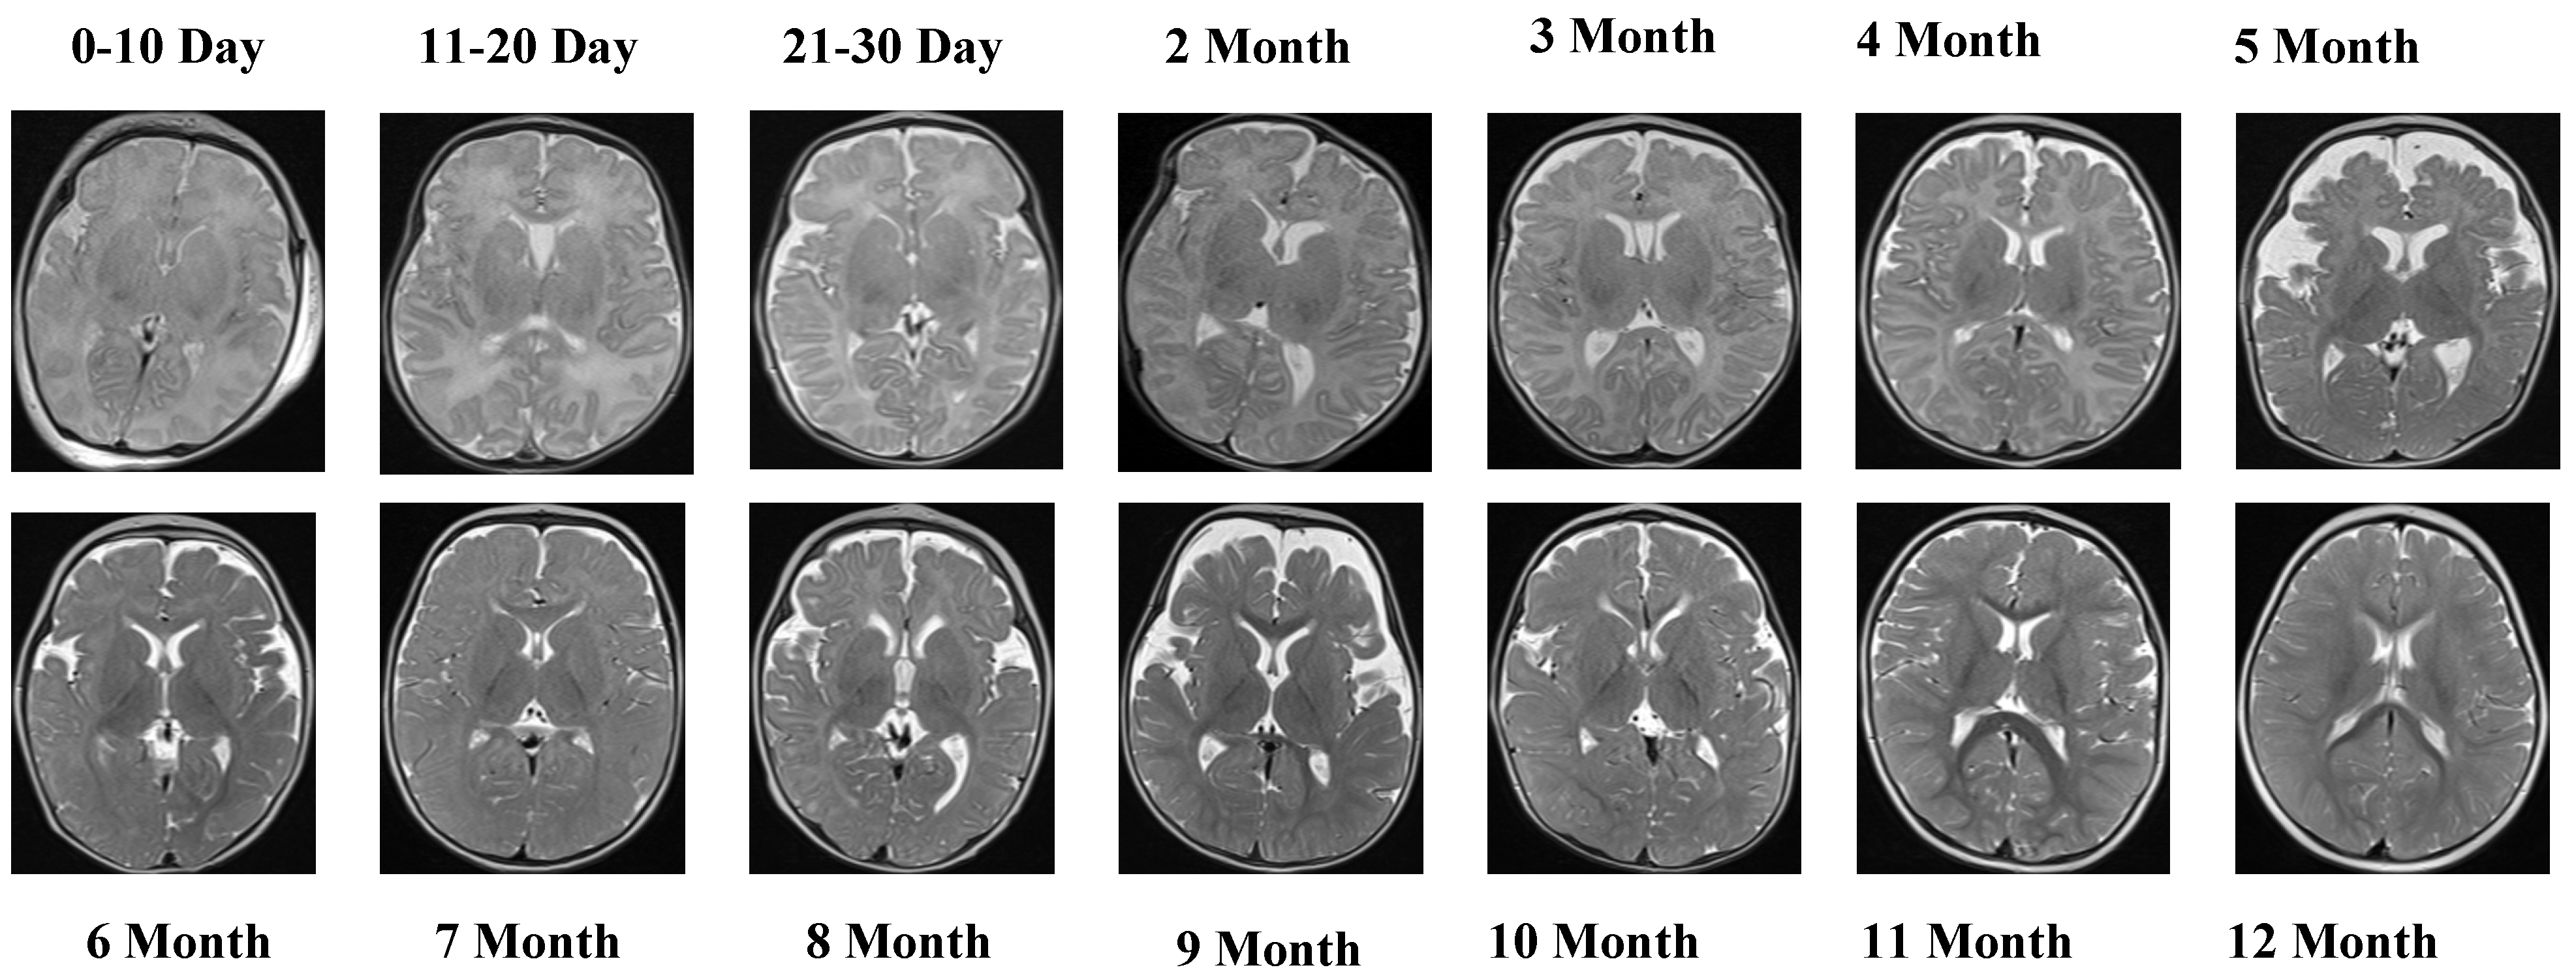

The T1 Female sequence comprised 7754 images, with 6205 used for training and 1549 for testing. Similarly to the male subset, the data follow the same chronological structure, ensuring comparability across sexes. This facilitates a robust evaluation of potential sex-specific developmental differences. Representative samples from the T2 Male sequence are provided in Figure 3, highlighting the contrast-specific features of T2-weighted imaging across developmental stages.

Figure 3.

The visual examples of the T2 Male sequence across all developmental groups.

Figure 3 provides visual examples of the T2 Male sequence across all developmental groups, demonstrating the contrast-specific advantages of T2 imaging.

The T2 Male sequence included a total of 7066 images, divided into 5653 training samples and 1413 test samples. Compared with T1 data, T2-weighted images offer complementary contrast that captures different tissue characteristics, enhancing the diversity of training features. Representative MRI slices from the T2 Female sequence are shown in Figure 4.